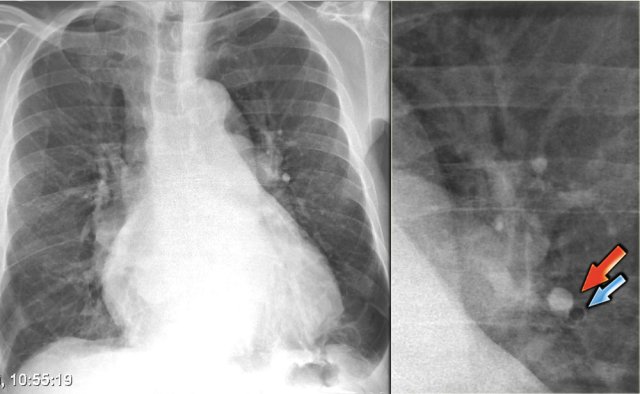

On the left a patient who was admitted with severe dyspnoe due to acute heart failure.

The following signs indicate heart failure: alveolar edema with perihilar consolidations and air bronchograms (yellow arrows); pleural fluid (blue arrow); prominent azygos vein and increased width of the vascular pedicle (red arrow) and an enlarged cardiac silhouette (arrow heads).

After treatment we can still see an enlarged cardiac silhouette, pleural fluid and redistribution of the pulmonary blood flow, but the edema has resolved.